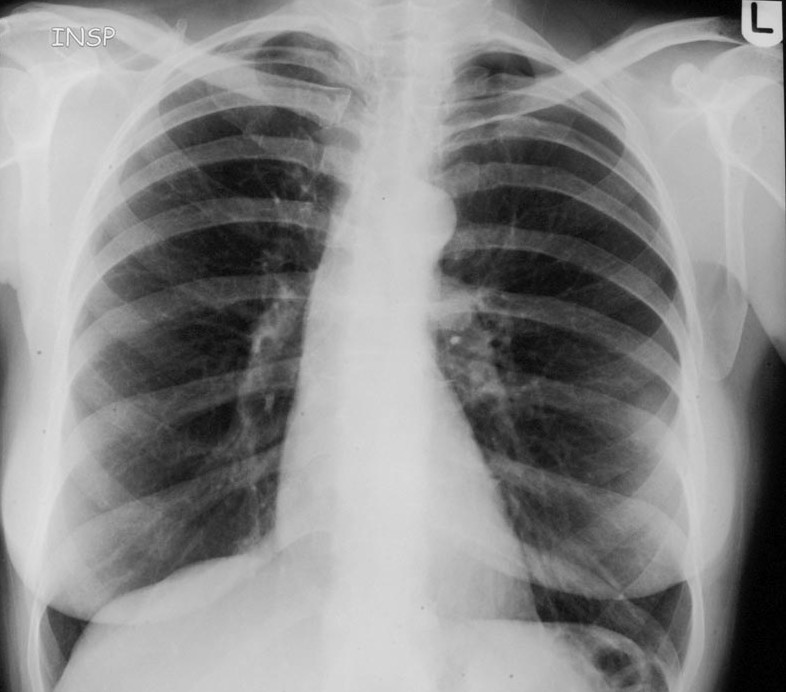

Figure 1From: Pneumothorax after a clinical breast fine-needle aspiration of a lump in a patient with Poland's syndromeCXR in inspiration showing left sided small pneumothorax.Back to article page